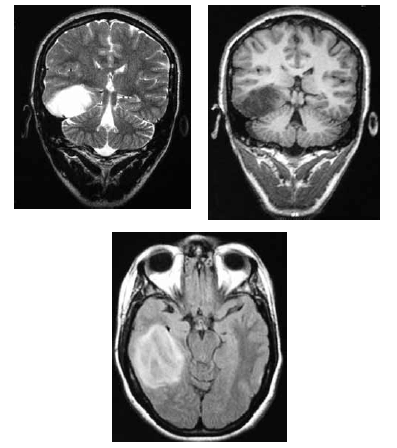

Uma mulher de 36 anos de idade foi encaminhada ao ambulatório de neurologia por dificuldade no controle das crises epilépticas. Ela referiu ter tido uma convulsão febril aos 36 meses e ter passado a ter crises em que ficava “fora do ar” aos 11 anos. Ela recebeu o diagnóstico de epilepsia generalizada do tipo ausência e foi-lhe prescrito fenobarbital. Desde então, já fez uso de primidona, ácido valpróico e diazepam, em monoterapia e associados ao fenobarbital, sem sucesso. No exame, a paciente apresentava um comprometimento da memória recente e aparentava ter um sutil deficit dos campos visuais e Babinski à esquerda. Apesar de trazer um EEG normal, foi solicitada RNM de encéfalo, que é reproduzida abaixo.

Com referência a esse quadro clínico, julgue os itens seguintes.

Uma mulher de 36 anos de idade foi encaminhada ao ambulatório de neurologia por dificuldade no controle das crises epilépticas. Ela referiu ter tido uma convulsão febril aos 36 meses e ter passado a ter crises em que ficava “fora do ar” aos 11 anos. Ela recebeu o diagnóstico de epilepsia generalizada do tipo ausência e foi-lhe prescrito fenobarbital. Desde então, já fez uso de primidona, ácido valpróico e diazepam, em monoterapia e associados ao fenobarbital, sem sucesso. No exame, a paciente apresentava um comprometimento da memória recente e aparentava ter um sutil deficit dos campos visuais e Babinski à esquerda. Apesar de trazer um EEG normal, foi solicitada RNM de encéfalo, que é reproduzida abaixo.

Com referência a esse quadro clínico, julgue os itens seguintes.

Uma mulher de 36 anos de idade foi encaminhada ao ambulatório de neurologia por dificuldade no controle das crises epilépticas. Ela referiu ter tido uma convulsão febril aos 36 meses e ter passado a ter crises em que ficava “fora do ar” aos 11 anos. Ela recebeu o diagnóstico de epilepsia generalizada do tipo ausência e foi-lhe prescrito fenobarbital. Desde então, já fez uso de primidona, ácido valpróico e diazepam, em monoterapia e associados ao fenobarbital, sem sucesso. No exame, a paciente apresentava um comprometimento da memória recente e aparentava ter um sutil deficit dos campos visuais e Babinski à esquerda. Apesar de trazer um EEG normal, foi solicitada RNM de encéfalo, que é reproduzida abaixo.

Com referência a esse quadro clínico, julgue os itens seguintes.